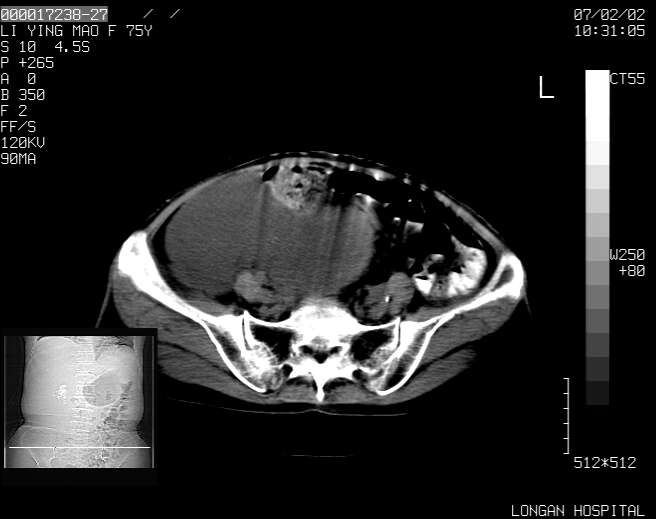

以下是引用dyqct在2007-2-10 8:53:00的发言:[br]考虑:1、肝脏多发囊肿[br] 2、左肾囊肿,右肾多发结石并积水。[br] 3、右胸少量积液。[br] 4、右肾周包裹性积液或淋巴管瘤(有见缝就钻的征象、薄隔、小结节状钙化)?[br] 5、腰椎动脉瘤样骨囊肿?[br] [br] [br]